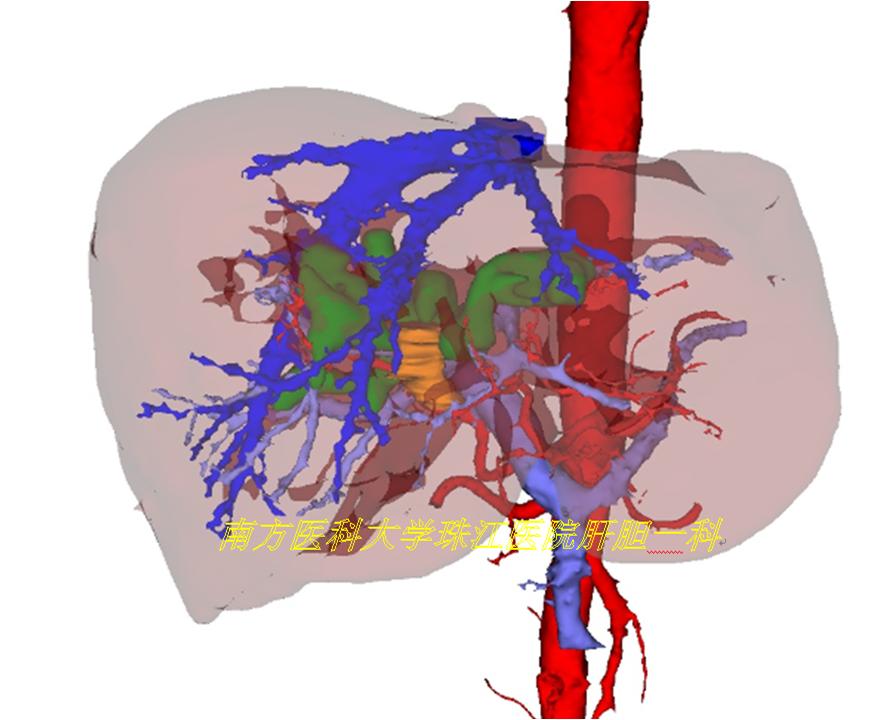

慕名前往,完成老李的三维可视化模型,发现肝动脉及门静脉均存在变异,如果术前未发现这两处变异,贸然进行手术很可能出现相关的并发症。

在三维可视化指导下,方驰华教授团队“顺藤摸瓜”成功地为老李进行肝门部胆管癌根治性切除术,术中情况跟术前三维重建模型完全一致。术后顺利康复出院。